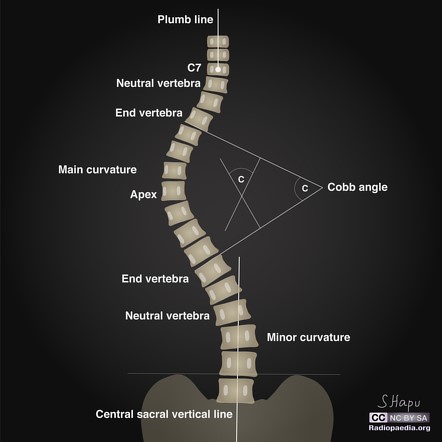

– Scoliosis,

КFS is diagnosed by clinical evaluation, identification of characteristic physical findings and specialized tests. Diagnosis begins with X-rays or other advanced imaging techniques, such as Magnetic Resonance, which shows fusion of the cervical vertebrae, open spaces (interspaces) between the vertebrae and possible pressure on the spinal cord. X-rays of the entire spine are performed to detect other spinal abnormalities. КFS can be associated with a wide range of abnormalities involving other parts of the body. Therefore, it is necessary to do:

Surgical intervention may be indicated for various reasons, such as persistent pain, neurological deficit, neck instability, spinal cord constriction or to correct severe scoliosis. Sometimes surgical intervention is needed to improve other skeletal anomalies, or those associated with the heart, kidneys, etc.

Our patient is thirty years old, with a fixed diagnosis of Klippel-Feil syndrome, thoracis scoliosis, pre-existential hypertension, deafness. At the age of one year, cheilognathopalatoschisis was corrected, nephrolithiasis was present.